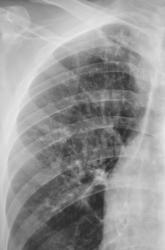

Иллюстрация 2. Слева определяется субтотальное снижение прозрачности легочного поля за счет наличия значительных размеров паракостального осумкованного выпота, имеющего чёткий и ровный контур. На фоне инфильтративно измененной легочной ткани в верхнем, среднем и нижнем легочных полях четко определяются две структуры — просветления с горизонтальными уровнями жидкости. Слева купол диафрагмы подтянут, фиксирован. Тень средостения резко смещена вправо.